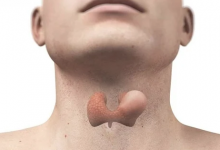

بروز الأوردة تحت الجلد.. الأسباب والعلاج

يلاحظ كثير من الأشخاص مع التقدم في العمر زيادة وضوح الأوردة تحت الجلد، خصوصًا في اليدين والساقين. ورغم أن هذه الظاهرة تُعد في معظم الحالات جزءًا طبيعيًا من الشيخوخة، فإنها تعكس تغيّرات تحدث في الجلد…